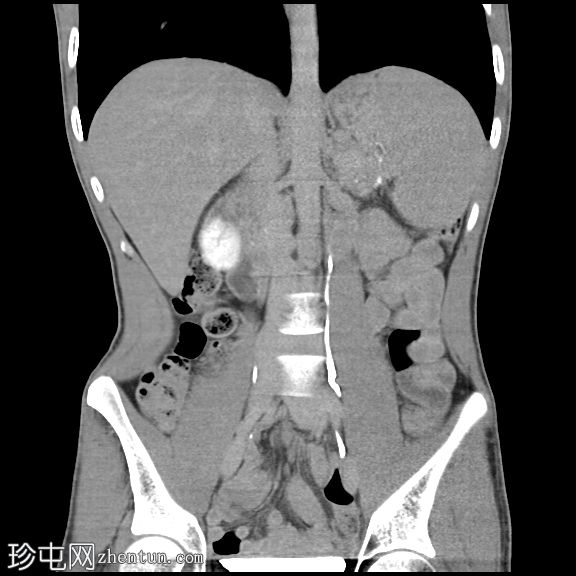

冠状位增强扫描

门静脉期

胰腺肿大。胰头、胰颈和胰体未见强化,边界不清且不规则。主胰管扩张,管内可见钙化。

胰腺实质内弥漫散在分布着大量钙化灶。

胰尾可见部分强化区域。

胰尾部钙化性假性囊肿。

影像学表现提示慢性钙化性胰腺炎伴胰尾部钙化性假性囊肿。

弥漫性实质及导管钙化是慢性钙化性胰腺炎的典型特征。

胰头及胰体无强化、形态不规则提示纤维化程度较重。

钙化性假性囊肿是一种慢性并发症,可通过囊壁钙化与肿瘤相鉴别。

CT是评估实质缺损、导管改变、钙化及假性囊肿的首选影像学检查方法。